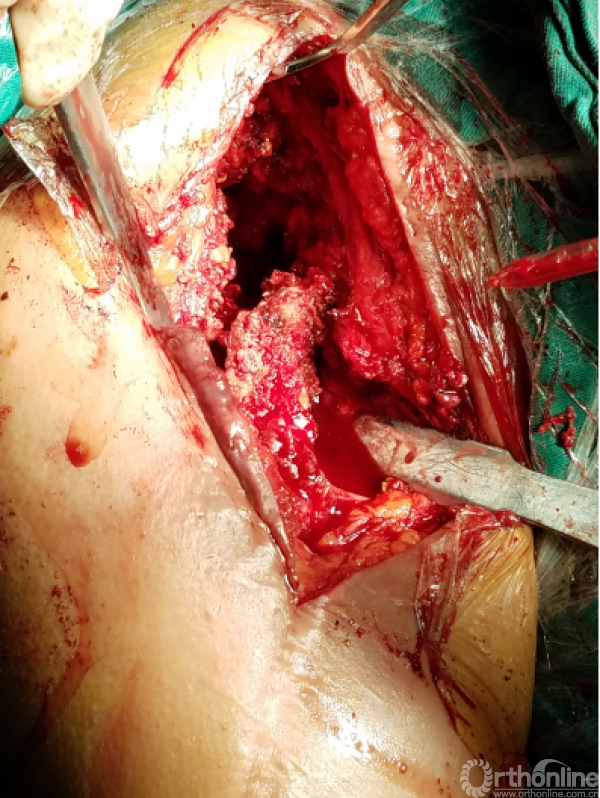

窦道周围见明显分泌物约10毫升

困难重重:

1、广泛粘连,解剖层次不清

2、广泛点状出血灶

3、分不清间隙

4、盂肱关节正常结构位置改变,关节囊瘢痕挛缩替代

5、屈曲外旋看不见关节间隙活动

手术过程:

1.从近端关节前外侧逐步下行,切除瘢痕

2.用食指逐步探查

3.以骨面硬质感为基准从中央部位向两侧分离

4.骨撬,骨膜剥离器协助分离内外侧间隙

5.以缺损处为中心向四周扩大显露

咬出增生骨痂及清理瘢痕组织后显露出原肩袖缝线,杂乱,完整,表面见有脓性组织

瘢痕发硬,变性,周围包裹纤维软骨痂

由于解剖结构紊乱,头静脉已消失。旋肱后动脉,弓状动脉剥离时出血,位于外侧转弯处,行填塞止血。

显露出肱骨头假体柄处

开始向内上扩大显露

注意事项: 肱骨头内移至喙突处,位于后内侧下方已有骨桥连接

特别小心腋鞘及臂丛神经

提示无法顺利脱位!!!

小心咬出间隙后,牵引肘关节前屈肩关节后伸外旋,拉钩撬拨脱位!!

关节盂正常结构消失,至喙突偏内侧部位,上方紧贴肩峰下,仍然有骨质可用!

咬除连接骨桥,清理髓腔,恢复活动度

安尔碘溶液反复冲洗1000毫升,浸泡!!!

1.关节盂正常结构消失,前倾增大。

2.紧贴喙突内侧

3.骨质菲薄

4.特别小心肌皮神经及腋鞘

骨质疏松明显,皮质成虫蚀样改变,外侧缺损。